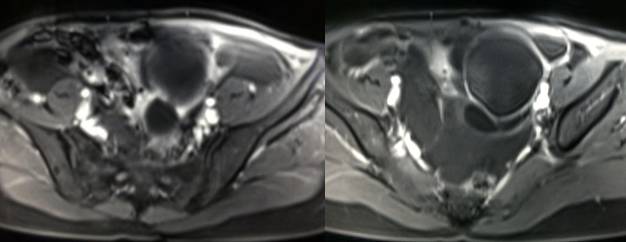

MR检查:

病理结果:黄体血肿

黄体血肿早期:囊内出血较多时,表现为卵巢内近圆形囊肿,囊壁厚,内壁粗糙。

黄体血肿中期:黄体血肿内血液凝固,部分吸收,囊壁变薄而,内壁光滑。

黄体血肿晚期:血液吸收后囊肿变小,转变为白体,内部回声呈实性稍高回

声,与周围卵巢组织分界不清,面靠彩超显示其周围环状血流判断,当血液完全吸收后形成黄体囊肿,囊壁变得光滑,与卵巢其他囊肿难以区分。

根据时间不同MR信号也有所不同,TIWI脂肪抑制序列能够鉴别脂肪和出血。